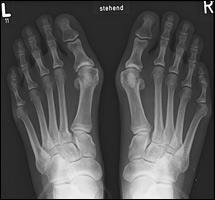

Τα αγαπημένα καλοκαιρινά μας υποδήματα μπορεί να δημιουργήσουν έντονες ενοχλήσεις στα νύχια των ποδιών και τα πέλματά μας. Δείτε τα συνηθέστερα σανδαλο-προβλήματα και πώς θα τα αντιμετωπίσετε.